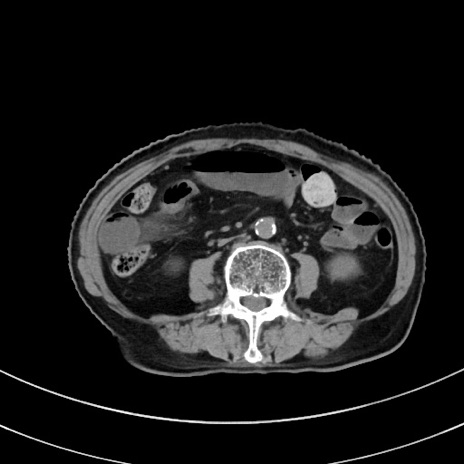

冠状断像

【症例】70歳代 女性

【主訴】心窩部痛

【現病歴】延髄病変の精査・加療にて神経内科入院中。本日より心窩部痛あり。

【身体所見】右下腹部を中心に圧痛と反跳痛あり。

【データ】WBC 10900、CRP 0.02